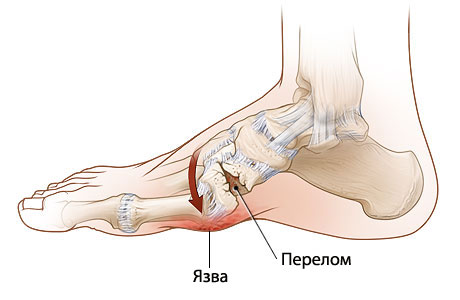

Для осложненной стадии болезни характерны деформации, присущие диабетической стопе. Кости, связки и мягкие ткани разрушаются, теряя свою функциональность. У пациентов развиваются трофические язвы, кожа на подошве утолщается и появляются болезненные трещины. Разрушение костей приводит к их фрагментации, что делает стопу похожей на мешок с костями на рентгеновском снимке.

Стопа теряет свою функциональность, и пациент утрачивает возможность самостоятельного передвижения, а образовавшиеся язвы не заживают.

Снижение плотности костной ткани может привести к трещинам и переломам. Ухудшение кровоснабжения мягких тканей способно вызвать трофические язвы. Инфицирование таких язв может привести к серьезным осложнениям, включая гангрену, флегмону, рожистое воспаление и остеомиелит.